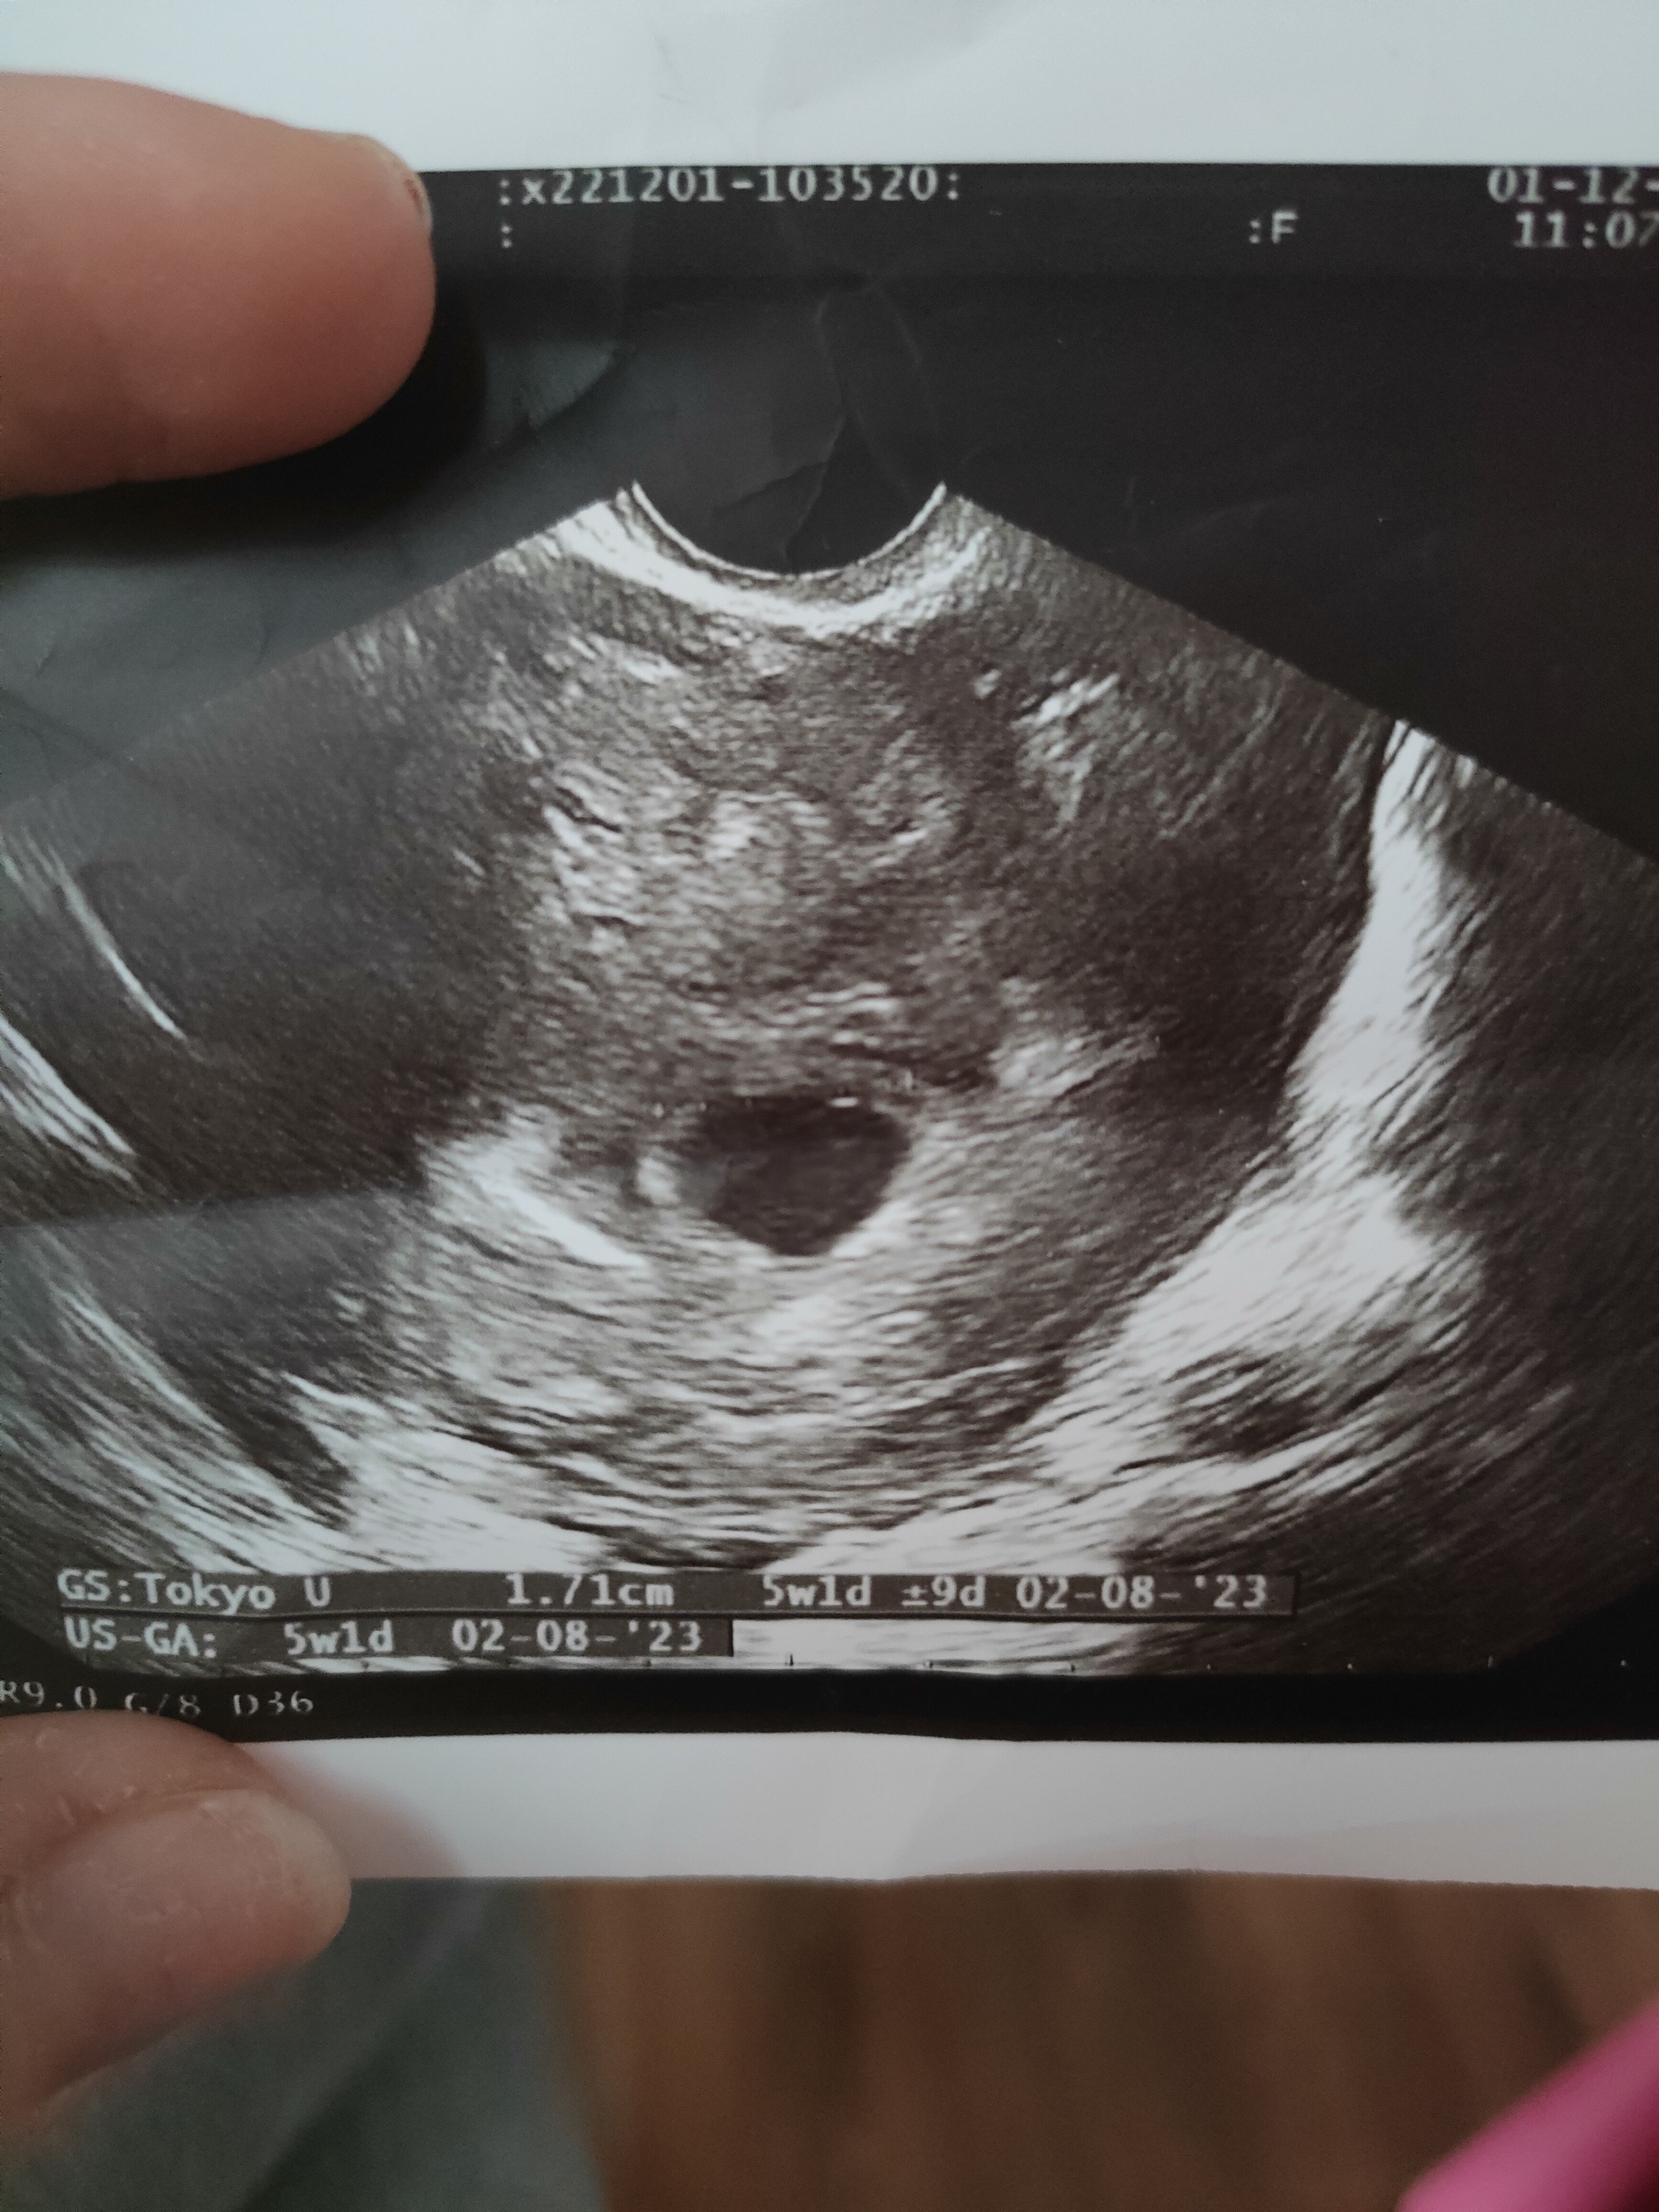

5 tydzień ciąży

Ale mój pecherzyk w tym tyg ma 17 cm chyba jest za duży aby w nim nic nie bylo

teoretycznie graniczne jest 25 mm. Natomiast najczęściej już pomiędzy 8 a 10 widać pęcherzyk żółtkowy. Póki co masz jeszcze chwilę natomiast jeśli to Ty wstawiłaś zdjęcie na innym wątku to tam jakość pozostawia wiele do życzenia więc możliwe, że nawet już coś tam jest

To moje

• IMG20221201120352.jpg